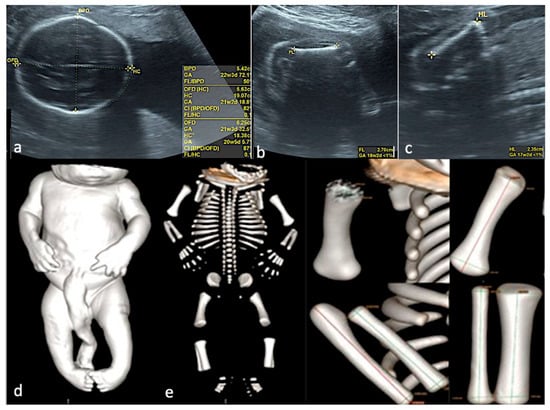

Figure 4. Rachischisis. The fetus presented with lower limb paralysis. (a)—2D conventional US, sagittal view of the fetus at FT anomaly scan, showing the lack of regularity of the overlying skin. (b,c)—3D surface rendering applied at FT anomaly scan: sagittal view of the fetus, showing normal intrafetal ratios, and frontal view from the posterior aspect, suggesting lumbar-sacral scoliosis and additional hemivertebra. (d)—postabortum specimen, macroscopic appearance. (e,f)—CT scan surface rendering, showing the skin defect and confirming the hemivertebra, the level and the extent of the spine anomaly.

Figure 5. Skeletal dysplasia. (ac)—Prenatal US data, showing severe intrafetal disproportions: biparietal diameter—corresponding to 22 weeks and 3 days, femur length—corresponding to 18 weeks and 2 days, humerus length—corresponding to 17 weeks and 2 days. (d)—CT scan of the specimen, surface rendering, confirming the severe intrafetal disproportions (very short long bones). (e)—CT, Cone Beam CT technique used, allowing each bone measurement.